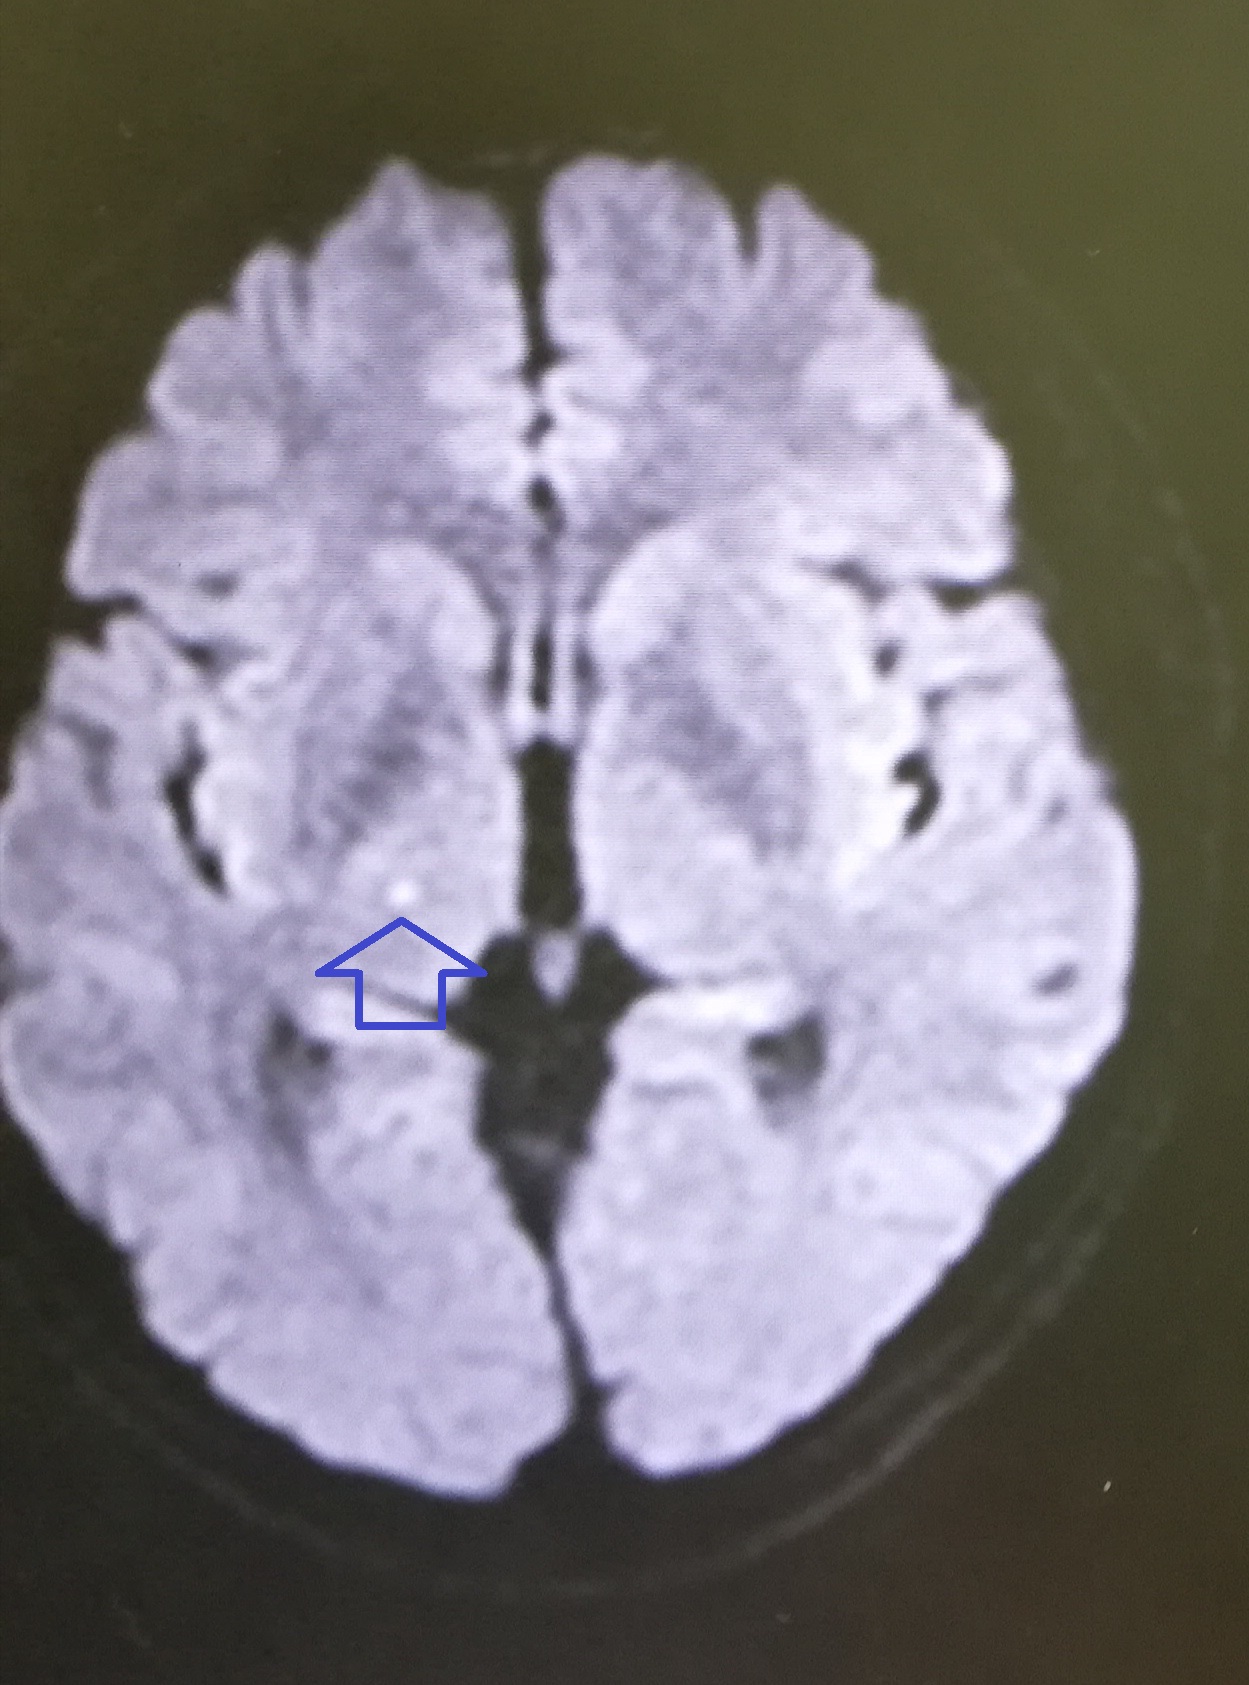

さて、9月1日の夜に救急車で運ばれてすぐに撮った脳のMRIの写真がこれです

こっちですね。

おそらく十中八、九僕の思い違いだと思うのですが、ほんのわずかですが薄く白くなっている箇所があるのです(上の写真のマウスのところ)。

もしよろしければ、もう一晩泊まって明日もう一度MRIを撮らせていただけませんか。

脳梗塞では発生したすぐにはMRIに写らないことが、ごくたまにあるようなのです。